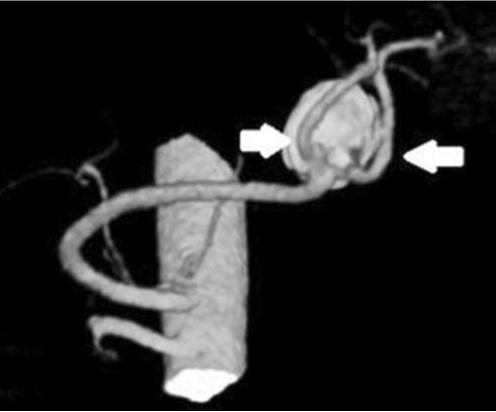

Fig. 2.

3D reconstruction CT image shows 2.2x2.0cm sized splenic artery aneurysm in which two large branching vessels (white arrows) are originating from the base of the aneurysm.

CT상 비장의 hilum의 위치에 2.5 x 2 cm 크기의 타원형의 mass like lesion이 관찰되었고 splenic artery와 연결되고 splenic artery와 동일한 조영증강을 보여 동맥류로 추정되었으며 rim calcification이 동반되어 있었음 (Fig.1). 정확한 해부 구조를 보기 위해 시행한 CT angiography에서 비장의 hilum의 근처 splenic artery 원위부에 동맥류가 관찰되었고 동맥류로부터 두 개의 큰 branching vessels이 기시하고 있었다 (Fig.2).